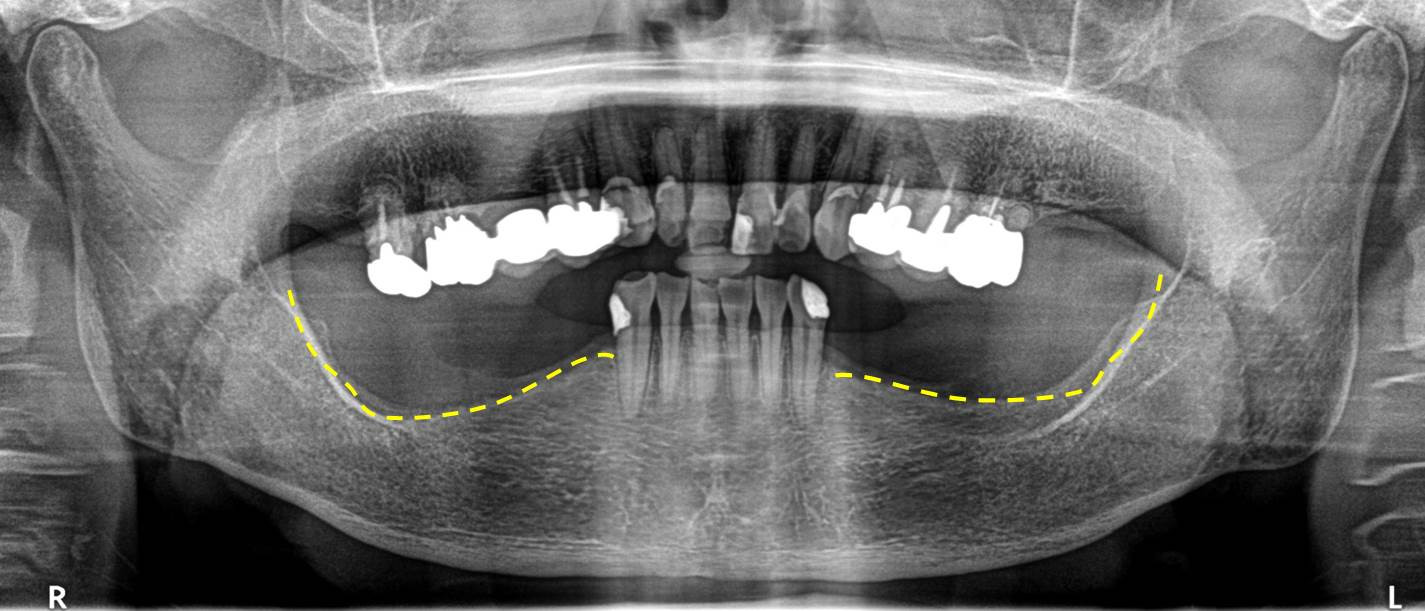

長期に使用することで顎堤(歯茎)や顎骨の異常吸収を生じることがあります。画像のレントゲン写真のように、臼歯部(奥歯)の顎骨が減り、スキーのジャンプ台のようになってしまっています。使用が出来ていても、気付かない間に経年的に身体に負担が生じている可能性があります。